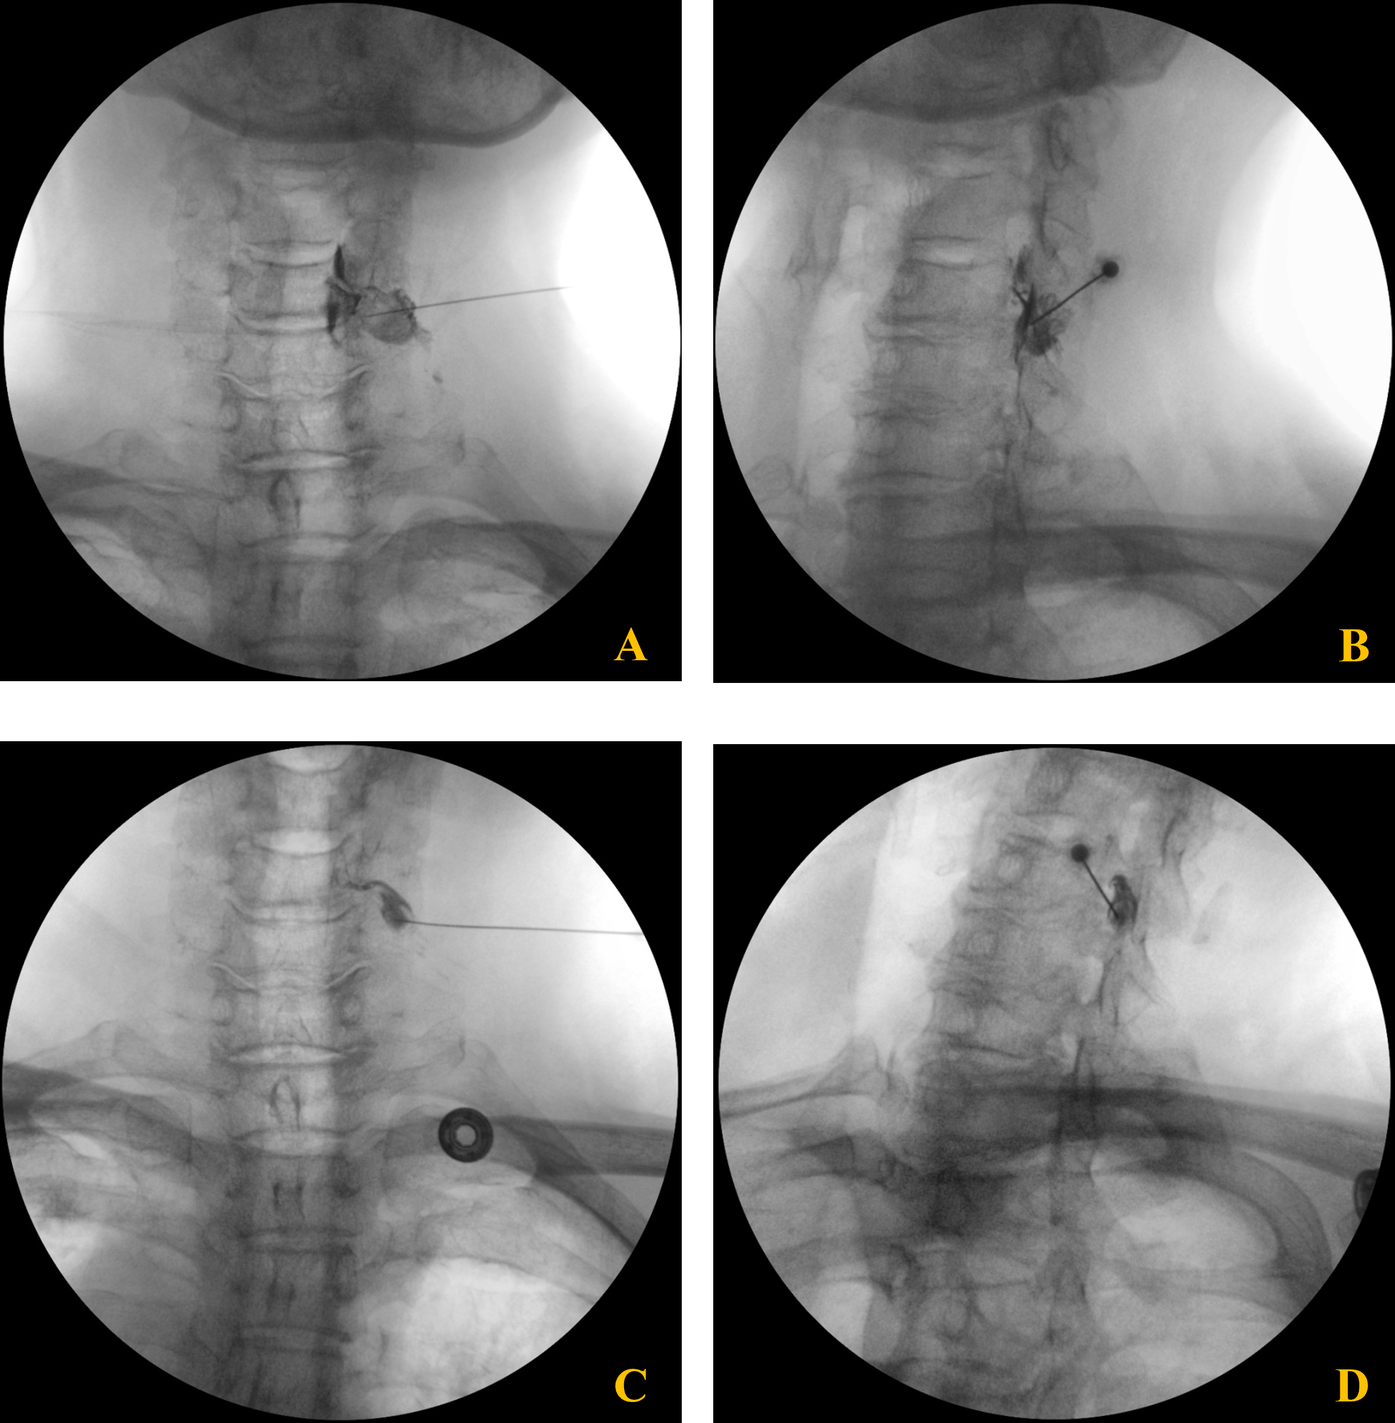

Radiographic evaluation included cervical spine x-rays, which showed multilevel degenerative changes such as reduced intervertebral disc height and osteophyte formation (10, 11). Cervical spine MRI revealed bilateral foraminal stenosis, most pronounced at C5–6–7-T1 on the right side, and a central disc protrusion at C4–5 (Figure 1) (12). There was no evidence of focal nerve root compression or abnormal signal change in the spinal cord.

Figure 1

Cervical spine MRI demonstrating right sided foraminal stenosis from C5 to T1. (A) Axial view showing cervical spinal canal and neural foraminal anatomy. (B) Right oblique view with visible cervical vertebrae (C4–C7) demonstrating right-sided foraminal stenosis. (C) Sagittal view showing the cervical spine alignment and neural foraminal narrowing.